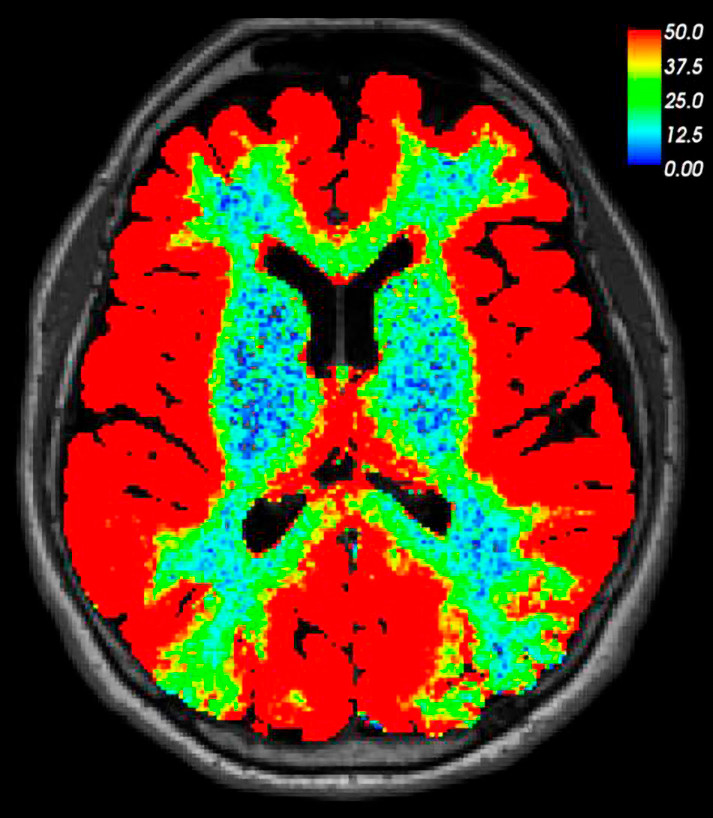

Dette MR-bildet av hjernen er tatt av en pasient 24 timer etter lumbalt innstikk og intratekal injeksjon av et MR-kontrastmiddel (0,5 ml gadobutrol). Pasienten var under utredning ved nevrokirurgisk avdeling på grunn av mistanke om kranial lekkasje av cerebrospinalvæske. Lekkasje kunne ikke påvises verken på bildet tatt etter 24 timer eller på tidligere tidspunkter. På dette bildet, som er basert på T1-vektet MR, har vi visualisert på en fargaskala den prosentmessige signaløkningen i hjernevevet som følger av kontrastanrikning. Bildet viser at et lite og vannløselig molekyl som gadobutrol kan anrike hele hjernen når det gis i spinalvæsken. Det har hittil vært uvisst i hvilken grad intratekalt injiserte legemidler kan anrike hjernevevet hos mennesker. Gitt at kontrastmiddelet ikke kan lekke inn i blodet gjennom den intakte blod–hjerne-barrieren, kan vi her slå fast at all anrikning av hjernen finner sted på utsiden av blodårene.

Siden de fleste legemidler gitt peroralt eller intravenøst ikke slipper ut gjennom blodåreveggene i hjernen, kan kunnskapen om veien inn til hjernen fra spinalvæsken åpne for nye måter å diagnostisere og behandle hjernesykdommer. Den kan også kaste lys over hvordan meningeale lymfeårer kan påvirke hjernen via cerebrospinalvæsken (1).

Mye tyder på at MR-kontrastmiddelet anriker hjernen via det såkalte glia-lymfatiske eller «glymfatiske» systemet, som ble beskrevet første gang i 2012 (2). Her fungerer spinalvæsken som et transportmedium for utskillelsen av avfallsstoffer som amyloid-β og tau-protein fra hjernen langs perivaskulærrommene (en form for «hjernevask»). Det er grunn til å tro at gadobutrol vaskes ut fra hjernen langs samme rute som disse avfallsstoffene. Ved glymfatisk MR er det vist at denne utskillelsen er redusert hos pasienter med en type demens (normaltrykkshydrocephalus) (3).